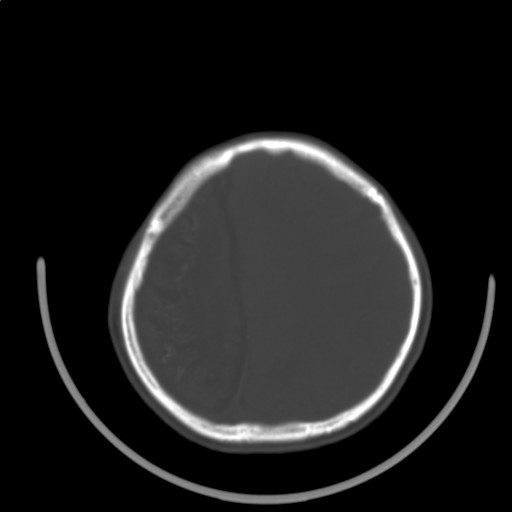

标题: PED3416:F,12Y,智力下降,学习成绩差,8个月时发过高烧。

右侧半球萎缩,软化,多量脑回样钙化,考虑颅面血管瘤病,建议dsa检查

右侧半球萎缩,软化,多量脑回样钙化,同侧颅盖板障增宽,考虑颅面血管瘤病,建议dsa检查与化脓性脑膜炎后遗改变鉴别。